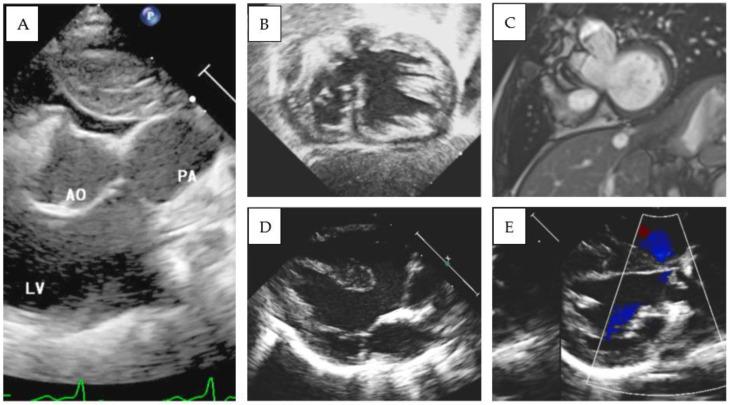

Double-outlet left ventricle (DOLV) is an abnormal ventriculo-arterial connection characterized by the origin of both great arteries from the morphological left ventricle. The aim of our paper is to describe the morphological and imaging features of DOLV and to assess the prevalence of the associated malformations and their surgical outcomes. METHODS From 2011 to 2022, we retrospectively reviewed the electronic case records of patients diagnosed with DOLV at the Bambino Gesu Children's Hospital. A systematic search was developed in MEDLINE, Web of Science, and EMBASE databases to identify reports assessing the morphology and outcomes of DOLV between 1975 and 2023. RESULTS: Over a median follow-up of 9.9 years (IQR 7.8-11.7 y), four cases of DOLV were identified at our institution. Two patients were diagnosed with (S,D,D) DOLV subaortic VSD and pulmonary stenosis (PS): one patient had (S,D,D) DOLV with doubly committed VSD and hypoplastic right ventricle, and another patient had (S,D,L) DOLV with subaortic VSD and PS (malposition type). Pulmonary stenosis was the most commonly associated lesion (75%). LITERATURE REVIEW: After systematic evaluation, a total of 12 reports fulfilled the eligibility criteria and were included in our analysis. PS or right ventricular outflow tract obstruction was the most commonly associated lesion (69%, 95% CI 62-76%). The most common locations of VSD were subaortic (pooled prevalence: 75%, 95% CI 68-81), subpulmonary (15%, 95% CI 10-21), and doubly committed (7%, 95% CI 4-12). The position of the great arteries showed that d-transposition of the aorta was present in 128 cases (59% 95% CI 42-74), and l-transposition was present in 77 cases (35%, 95% CI 29-43).

双出口左心室(DOLV)是一种异常的心室-动脉连接,其特征为两大动脉均起源于形态学上的左心室。本文的目的是描述双出口左心室的形态学和影像学特征,并评估相关畸形的患病率及其手术结果。方法:2011年至2022年,我们回顾性分析了在 Bambino Gesu儿童医院诊断为双出口左心室的患者的电子病历。在 MEDLINE、科学网和 EMBASE数据库中进行了系统检索,以识别 1975年至 2023年期间评估双出口左心室形态学和结果的报告。结果:在中位随访 9.9年(四分位间距 7.8 - 11.7年)期间,我们机构共识别出 4例双出口左心室患者。2例患者被诊断为(S,D,D)型双出口左心室合并主动脉下室间隔缺损和肺动脉狭窄(PS):1例患者为(S,D,D)型双出口左心室合并双室连接室间隔缺损和右心室发育不良,另 1例患者为(S,D,L)型双出口左心室合并主动脉下室间隔缺损和 PS(位置异常型)。肺动脉狭窄是最常见的相关病变(75%)。文献综述:经过系统评估,共有 12篇报告符合纳入标准并纳入我们的分析。肺动脉狭窄或右心室流出道梗阻是最常见的相关病变(69%,95%CI 62 - 76%)。室间隔缺损最常见的位置是主动脉下(合并患病率:75%,95%CI 68 - 81)、肺动脉下(15%,95%CI 10 - 21)和双室连接(7%,95%CI 4 - 12)。大动脉的位置显示,128例(59%,95%CI 42 - 74)存在主动脉 d-转位,77例(35%,95%CI 29 - 43)存在 l-转位。